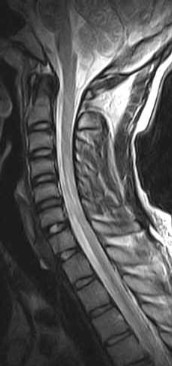

• There is a loss of the normal ventral bulge (flattened) of the cervical spinal cord, more so to the right over the C5 to C7 levels. Hyperintense signal, best appreciated on the GRASS axial images is seen within the cervical spinal cord, ventrally (anterior horn cells) over these levels.